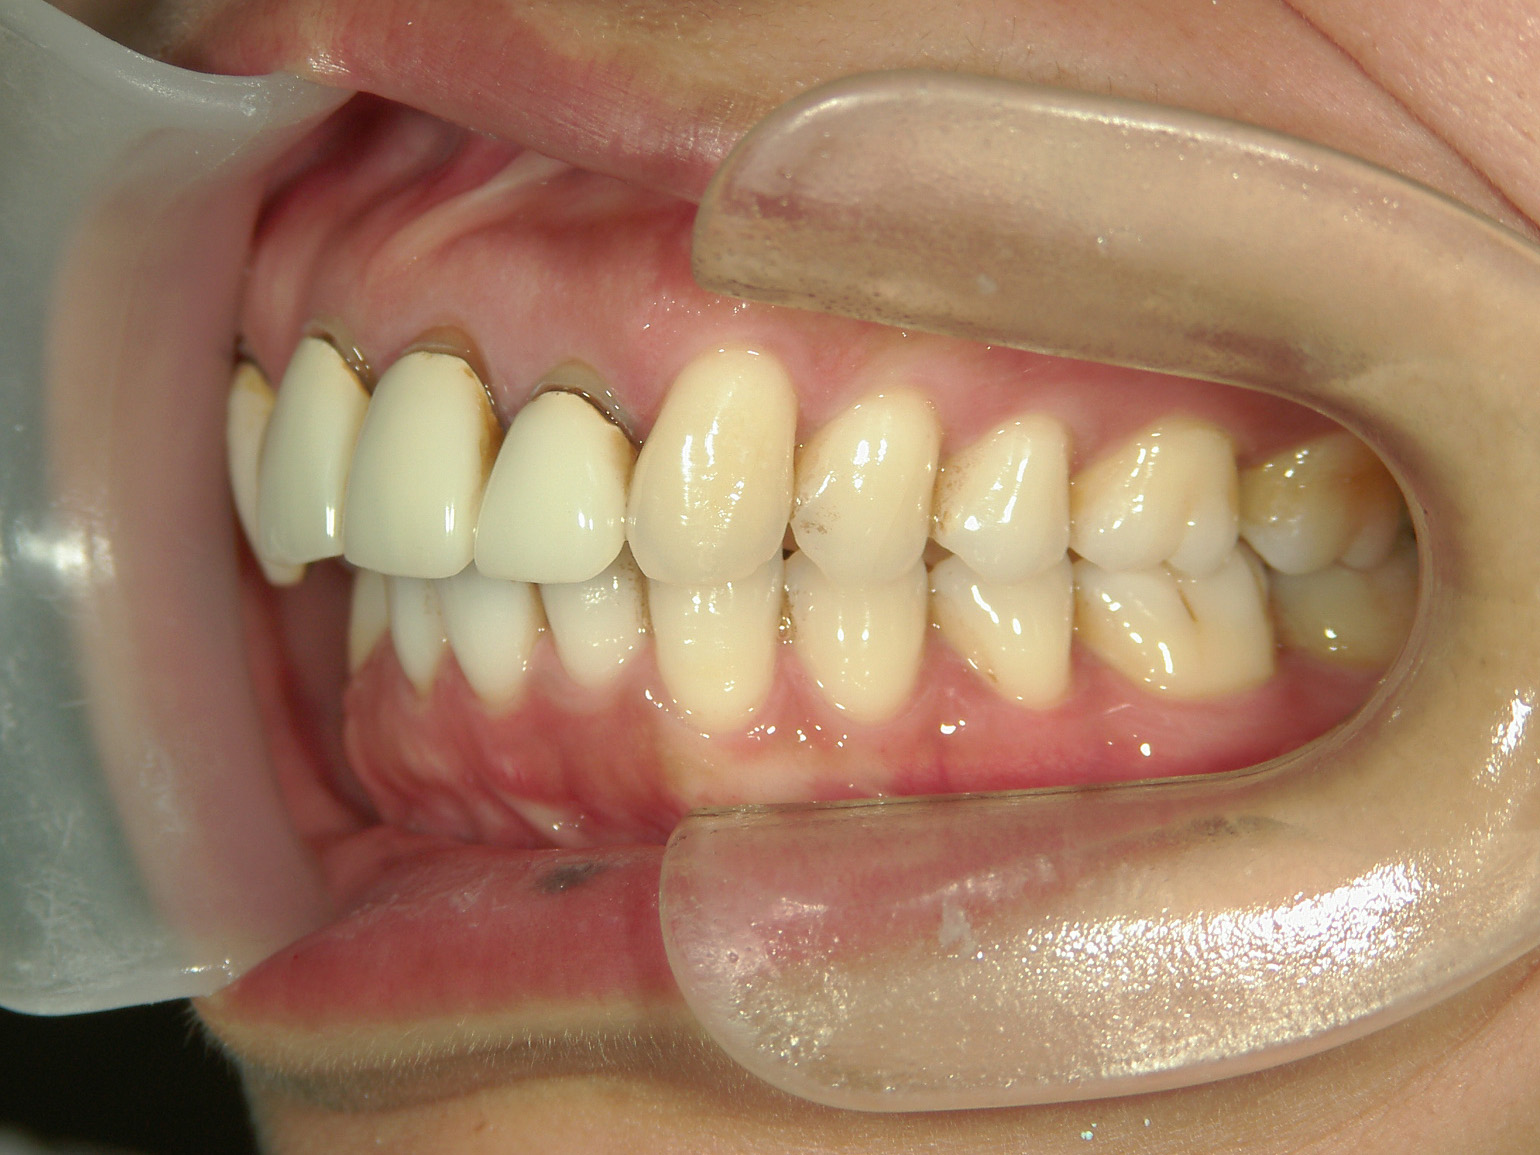

全顎ワイヤー矯正 症例(82)

主訴: 前歯の歯並びが気になる。

上下左右 第一小臼歯(4本)、左右上 親不知(2本)を抜歯。

ミニインプラント、アップライトスプリングを併用。

矯正前に左右上前歯4本を仮歯に変え、矯正治療後にセラミック(SHT)に冠せなおしました。

カテゴリー : ガタガタ(叢生)